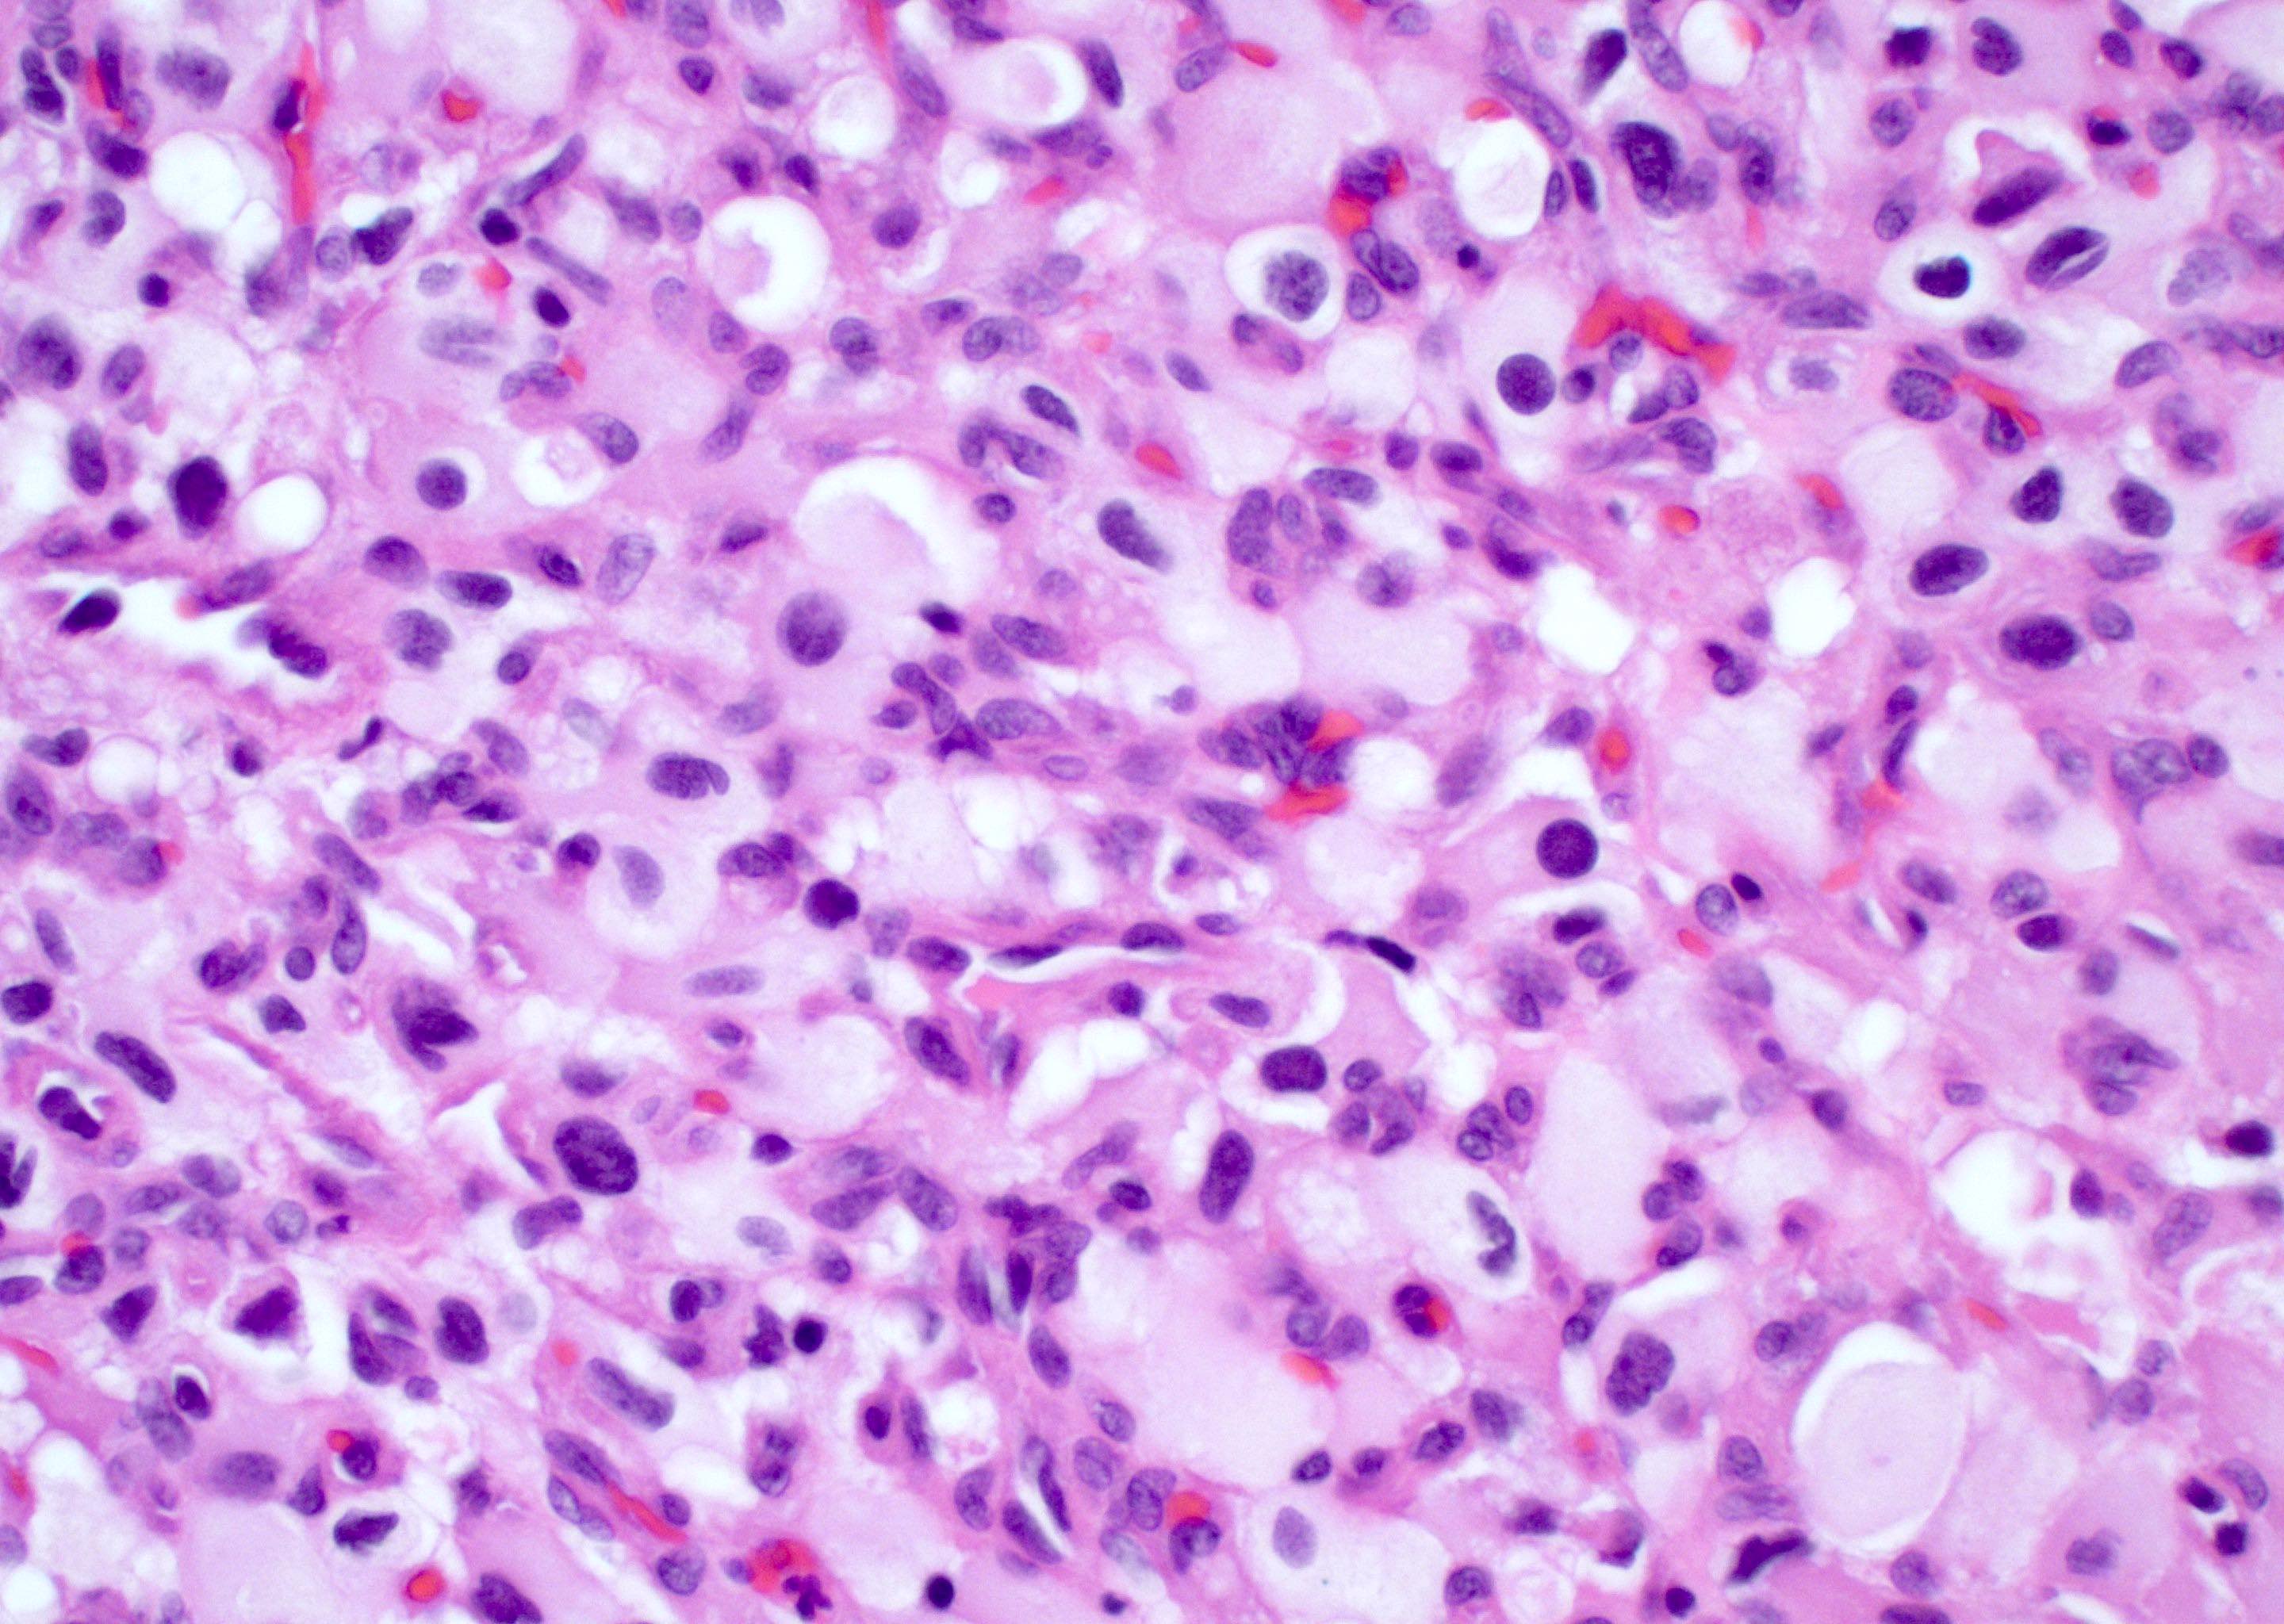

Microscopic (histologic) description

- Infiltrating, hypercellular astrocytic neoplasm often with hyperchromatic, elongated nuclei and irregular nuclear membranes

- Necrosis: can be geographic or pseudopalisading with neoplastic cells surrounding central necrosis

- Variable cell morphology: undifferentiated / primitive neuronal cells, astrocytic, gemistocytic, oligodendroglial-like, small cell, lipidized, granular, epithelioid, giant cells, mesenchymal metaplasia and epithelial metaplasia

- Lipidized / xanthomatous cells: cells with abundant foamy cytoplasm

- Be sure to exclude pleomorphic xanthoastrocytoma

Microscopic (histologic) images

Contributed by Bharat Ramlal, M.D. and Meaghan Morris, M.D., Ph.D.